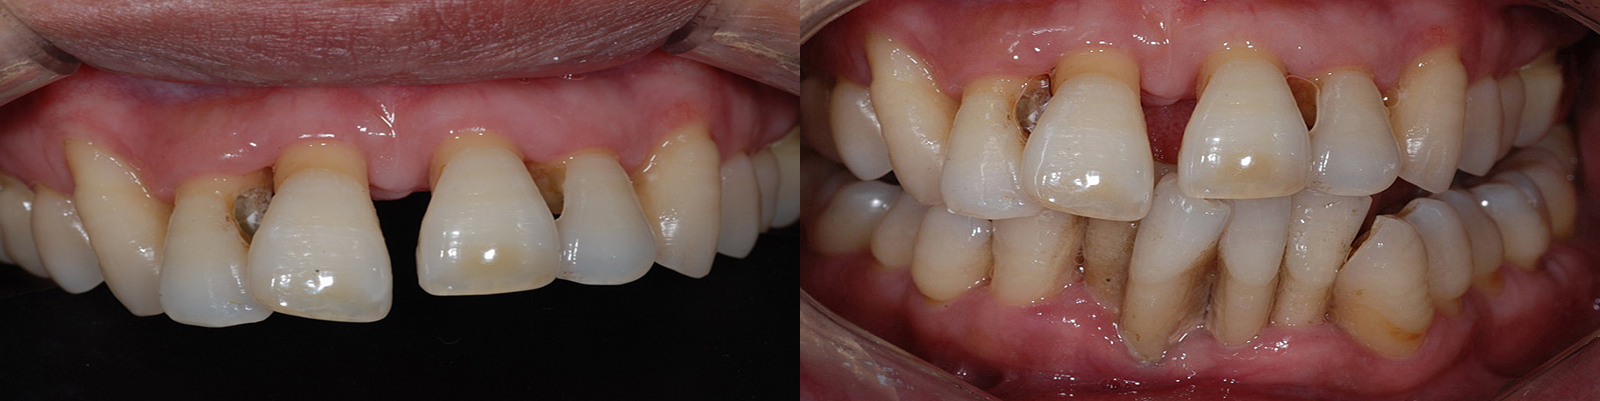

현재 잇몸이 좋지 않아서 흔들거리고,

빼야 되는 것처럼 보이는 치아들도

치주치료를

하고나면

발치하지 않고 치아의 수명을

연장할 수 있게 되는 경우도 많습니다.